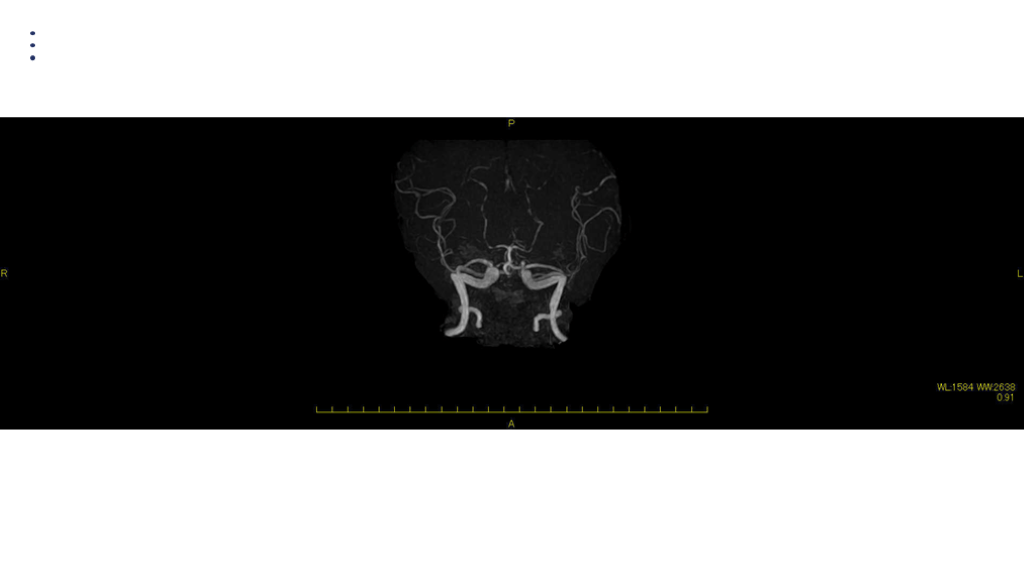

画像 所見 DAY 30 MRA 改善